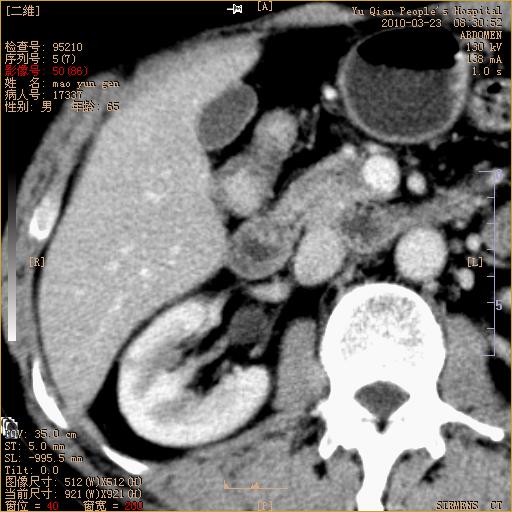

标题: CT25266:消瘦月余,前来肝部检查,请看看肠腔 [打印本页]

标题: CT25266:消瘦月余,前来肝部检查,请看看肠腔

肝区结肠占位,腺癌可考虑,建议肠镜活检。

升结肠肠壁增厚,不均强化,考虑升结肠腺癌可能性,建议肠镜检查。

1)考虑升结肠癌。2)右肾小囊肿。